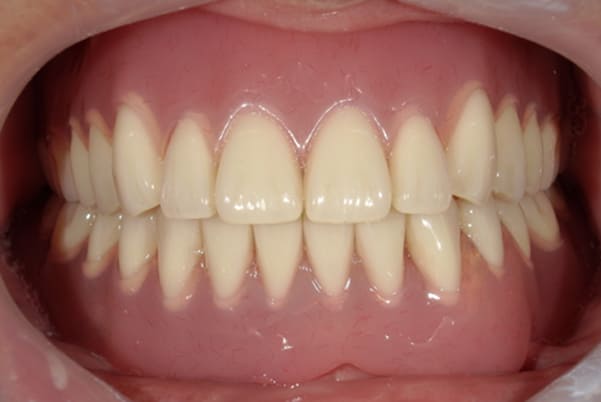

治療前後の口元の比較

こちらは、口を少し開いた時の治療前と治療後の

口元です。

正面から見た時にクラスプが目立たないように、

歯ぐきになじむ素材にて入れ歯を製作し、痛くなく自然に馴染み快適に生活を送れるようになりました。